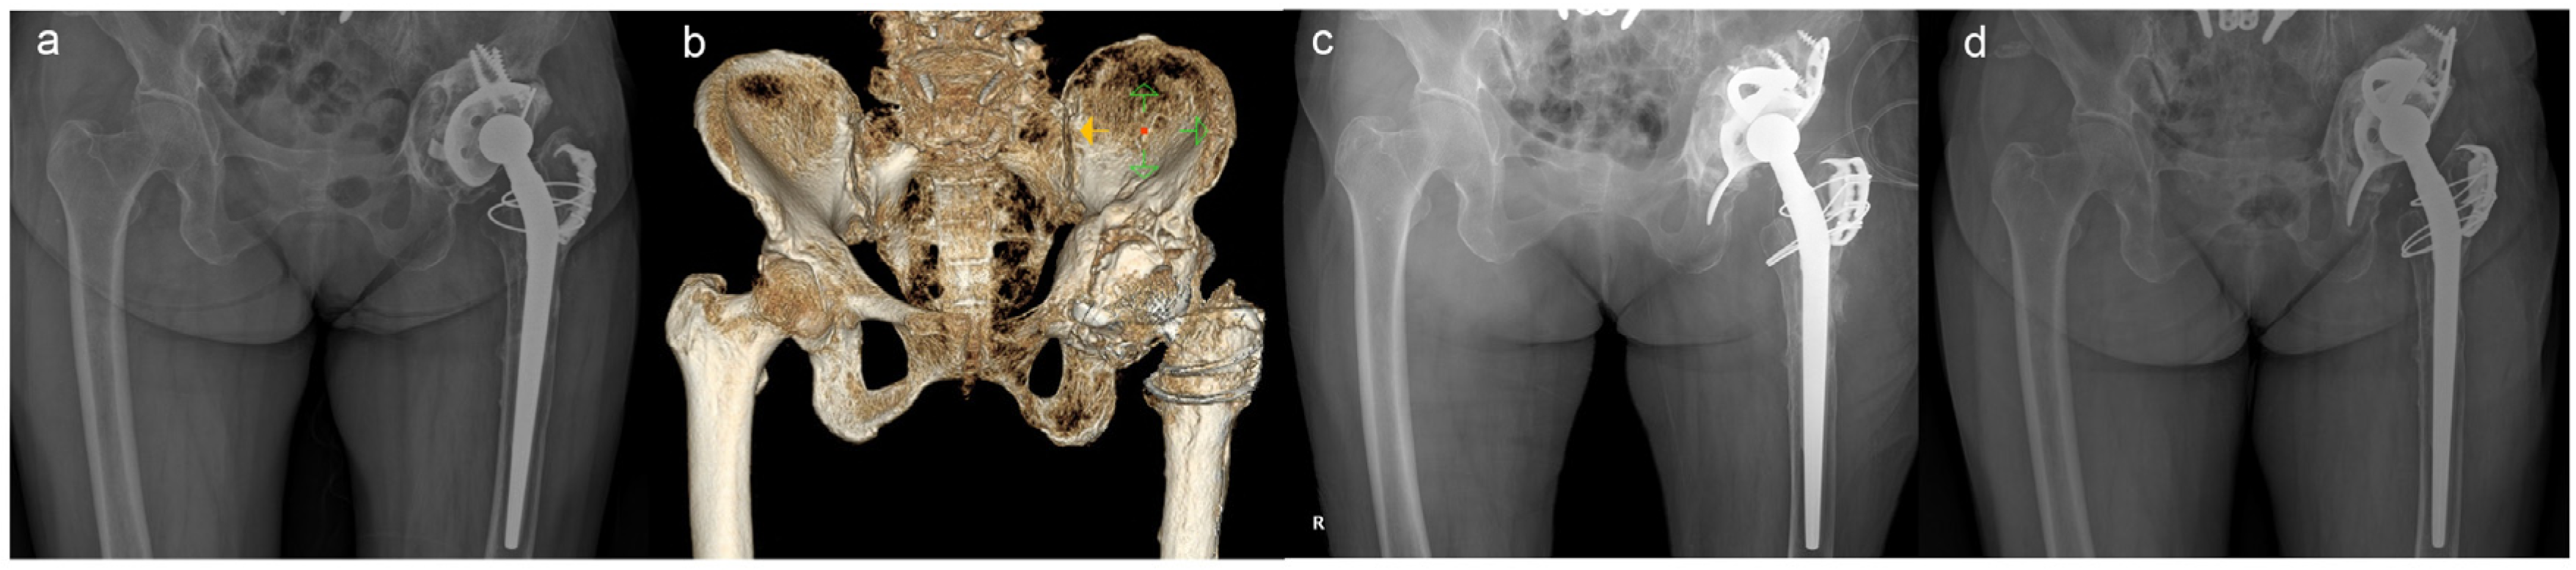

| Case | Sex/Age | BMI * (kg/m2) | BMD * (T-Score) | Reason for Index Surgery | Reason for Final Revision Surgery | No. of Revision Surgery | Follow-Up Duration (Months) |

|---|---|---|---|---|---|---|---|

| 1 | F/44 | 24.1 | −1.1 † | Traumatic OA | Cup loosening | 2 | 112.0 |

| 2 | M/71 | 21.6 | −3.3 | Femoral Neck Fx | All component loosening | 3 | 112.0 |

| 3 | F/69 | 34.1 | −2.1 | Traumatic OA | Cup loosening | 2 | 106.7 |

| 4 | M/65 | 28.1 | −2.6 | Femoral Neck Fx | All component loosening + ceramic liner Fx | 1 | 96.0 |

| 5 | M/58 | 26.3 | −1.0 | Traumatic ONFH | Acetabular destruction after monobloc arthroplasty | 1 | 112.0 |

| 6 | M/50 | 29.0 | 0.9 | Idiopathic ONFH | Cup loosening | 2 | 107.9 |

| 7 | M/75 | 21.7 | −1.9 | Traumatic ONFH | All component loosening + ceramic liner Fx | 3 | 100.0 |

| 8 | F/71 | 26.2 | −3.1 | Traumatic OA | Cup loosening | 4 | 101.1 |

| 9 | M/60 | 24.9 | −0.7 | Septic Hip Sequalae | Cup loosening | 1 | 99.6 |

| 10 | F/80 | 19.5 | −2.8 | LCP Sequalae | Cup loosening | 3 | 96.0 |

| Case | Side | Operation | Paprosky | Implants | Additional Procedure | Final HHS | Postop Cx |

| 1 | Lt | Total a | 3A | B-S + TM + Mesh | GTO + Grip plate | 85 | - |

| 2 | Lt | Total | 3A | B-S + TM | Trochanter wiring | 91 | - |

| 3 | Lt | Cup b | 3B | B-S + TM | - | 73 | PJI |

| 4 | Lt | Cup | 3B | B-S + TM | - | 72 | Acute D/L |

| 5 | Lt | Total | 3A | B-S + TM | ETO + Wiring | 86 | - |

| 6 | Lt | Cup | 3A | B-S + TM | GTO + Grip plate | 90 | - |

| 7 | Lt | Cup | 3A | B-S + TM | - | 81 | - |

| 8 | Lt | Cup | 3A | B-S + TM | GTO + Grip plate | 79 | - |

| 9 | Lt | Cup | 3B | B-S + TM | GTO + Grip plate | 82 | - |

| 10 | Rt | Cup | 3B | B-S + TM + Mesh | GTO | 76 | - |